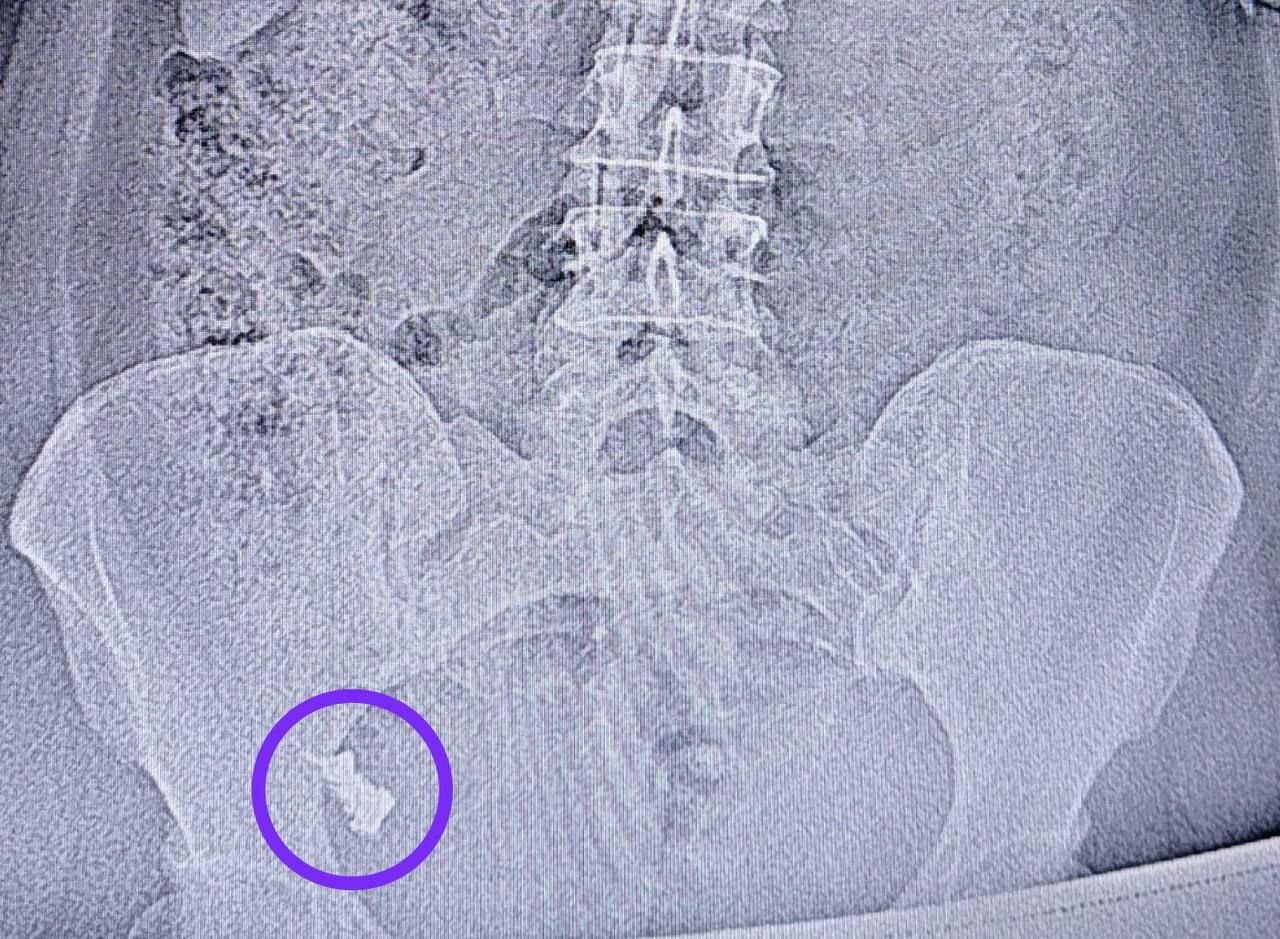

В Казани врачи спасли 50 летнюю женщину с зубным протезом в кишечнике Она проглотила имплант и долгое время отказывалась от извлечения с помощью эндоскопа надеясь на то что он выйдет сам В итоге через неделю ее госпитализировали А обследование показало что протез застрял в области перехода тонкой кишки в толстую Врачи достали его из труднодоступного места Операция прошла под анестезией и безболезненно для пациентки Читайте Газету Ru в MAX Участвуйте в розыгрыше

Врачи извлекли зубной протез из кишечника через задний проход 50 летняя жительница Казани случайно проглотила зубной протез Несмотря на рекомендации медиков пройти ФГДС и лечь в больницу женщина несколько раз отказывалась уверяя что инородный предмет выйдет самостоятельно Через неделю из за сильных болей пациентку всё же доставили в хирургическое отделение РКБ Обследование показало что протез застрял на границе тонкого и толстого кишечника Во время колоноскопии эндоскопист аккуратно извлёк протез Процедура проходила под контролем анестезиолога реаниматолога и благодаря анестезии прошла безболезненно для пациентки Подписаться Новости Казани